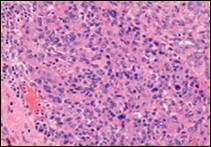

Ultrastructural evaluation is devoid of pertinent cellular features. However, modified endothelial cells, smooth muscle cells, striated muscle cells, histiocyte- like cells, fibroblast- like cells and miniature, interdigitating cellular processes conjoined by desmosome- like junctions are discerned5, 6. Figure 1, Figure 2, Figure 3, Figure 4, Figure 5, Figure 6, Figure 7, Figure 8.

Figure 2.Angiomatoid fibrous histiocytoma delineating sheets of spindle-shaped cells with bland nuclei and moderate cytoplasm disseminated in a vascularized stroma and a cuff of lymphoid cells 9.